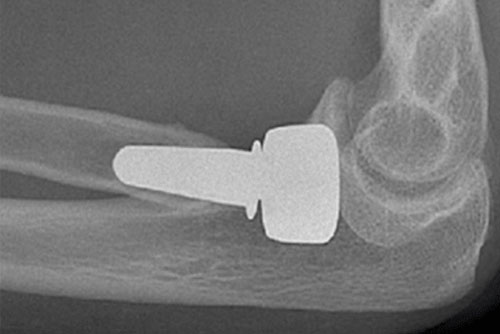

Radial head replacement is a surgical procedure performed to restore stability and movement to the elbow after a complex fracture or damage to the radial head. When the bone is too severely fractured to repair with screws or plates, the damaged portion is removed and replaced with a small artificial implant. This prosthetic helps maintain joint function, reduce pain, and allow the elbow to move more naturally. In some cases, surrounding ligaments that support the elbow are also repaired during surgery.